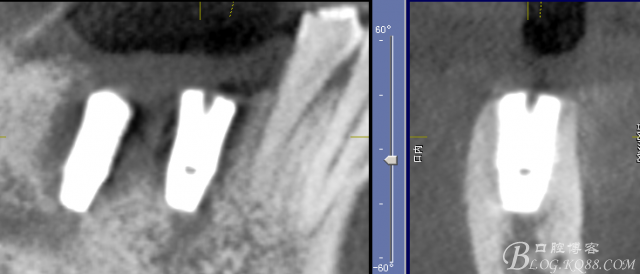

三維檢查種植體位置,方向,平行度

頰側(cè)軟組織凹陷明顯

切開,成骨情況良好,